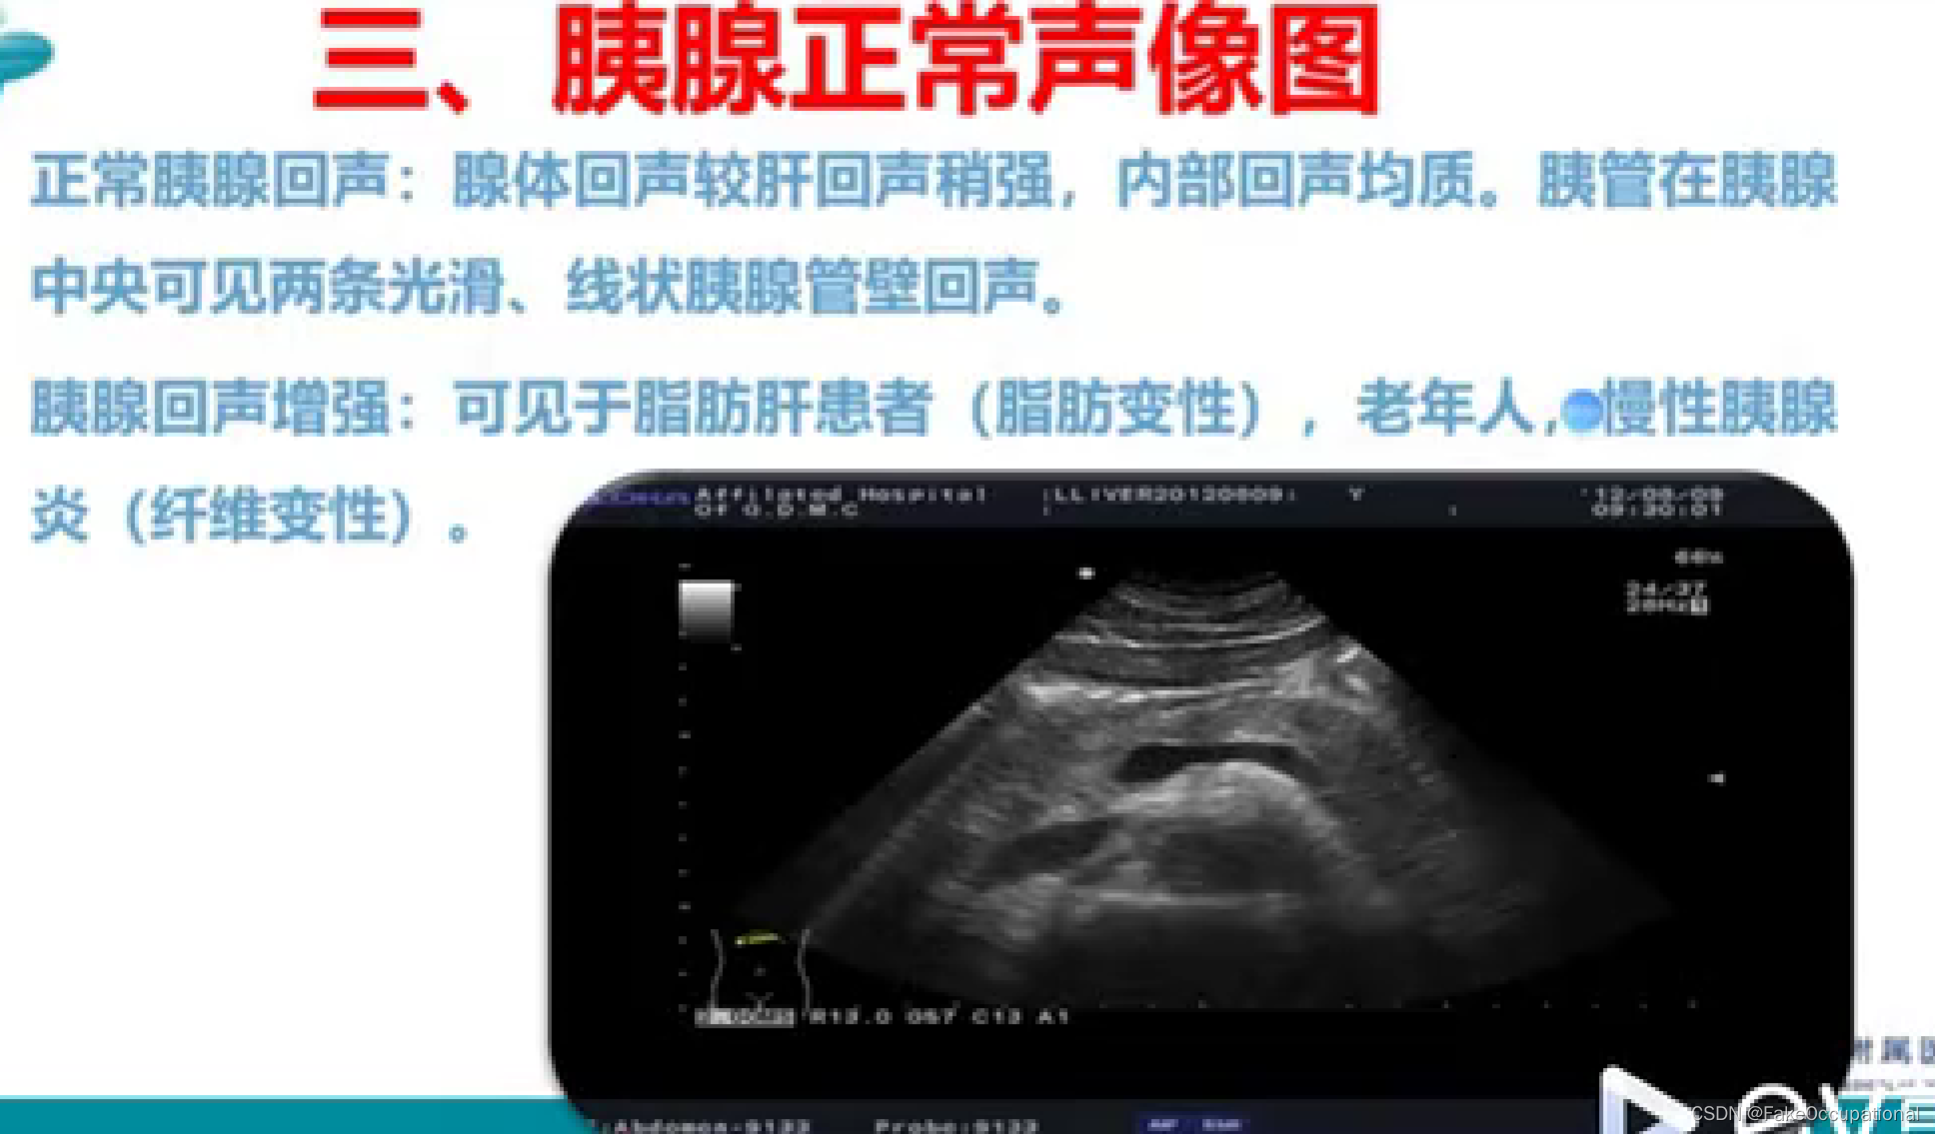

异常胰腺超声

二、探测方法

1、检查前的准备:

一般空腹8小时以上,如有腹胀或便秘者可灌肠或适当使用腹泻剂也可饮水400-600m,以胃作透声窗来观察胰腺

2、体位:

仰卧位为主,胃肠气干扰严重或体瘦者可用左、右侧卧位或半坐位

3、仪器:对仪器没有特殊要求,探头频率以2.5-5.0MHZ.

4、测量方法

上腹部横切扫查,切线测量法:

下腔静脉前方测量胰头,腹主动脉前方测量胰体,脊柱左侧缘测量胰尾。

5、正常值: (个体差异较大,数据仅供参考)

胰头<2cm,2-2.5cm疑大,22.5cm,肿大。>胰体尾部<1.5cm,1.6-2cm疑大,z2cm,肿大.>蝌料形胰头最大值可达3.5cm,而哑铃形及腊肠形胰尾可

达2.5cm

》主胰管在体部内径>0.2cm,可考虑胰管扩张